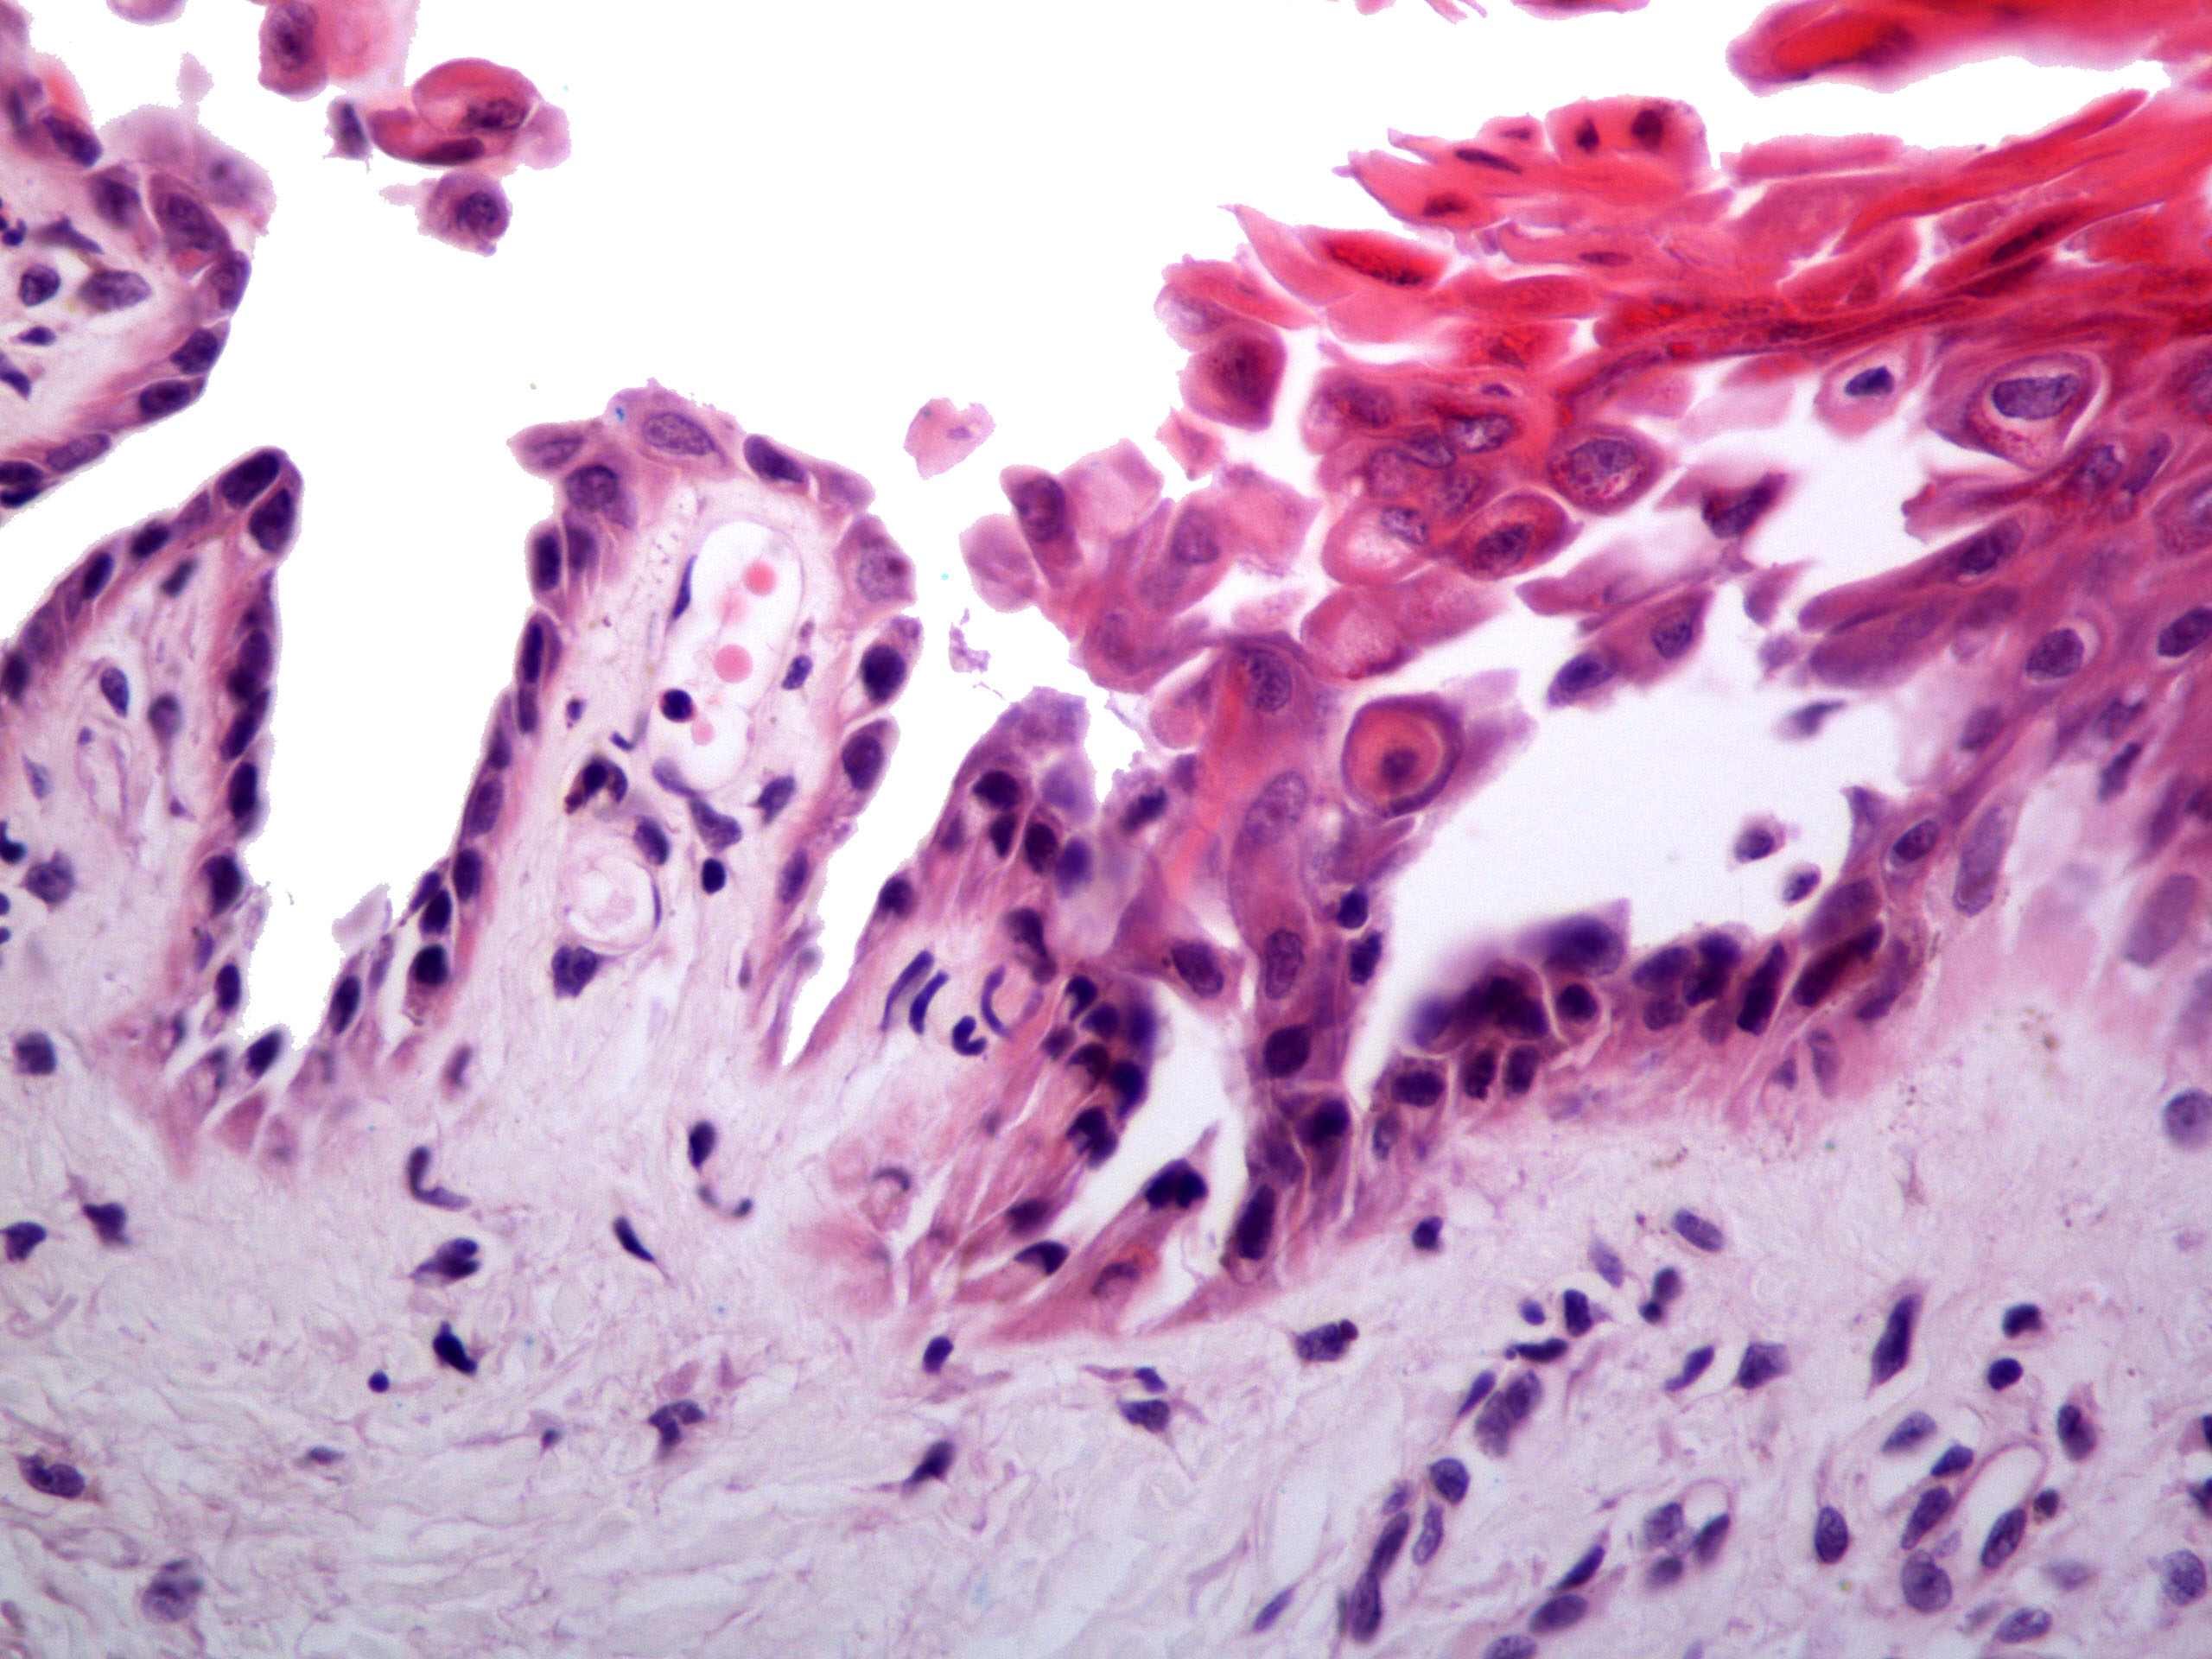

Microscopic (histologic) description

- Parakeratosis

- Variable epidermal thickness

- Acantholysis with characteristic dyskeratosis forming corp ronds and grains

- Corp rond: rounded keratinocyte in superficial spiny and granular layer with basophilic / pyknotic nucleus, perinuclear halo and often a rim of eosinophilic cytoplasm (J Dermatol 2017;44:232)

- Grain: elongated keratinocyte in the stratum corneum with small basophilic nuclei and intensely pink cytoplasm; appears as plump parakeratosis; may form tiers (J Dermatol 2017;44:232)

- Corp rond and grain type dyskeratosis is classical but not specific for Darier disease (see Differential diagnosis)

- Suprabasal acantholysis and clefting with retained single layer of basal keratinocytes overlying dermal papillae which appear to project into the acantholytic cavity (villi) (J Dermatol 2016;43:275)

- Frank bullae may occur in cases with extensive acantholysis and large clefts (Arch Dermatol 1982;118:278)

- Variable mild perivascular inflammatory cell infiltrate

Microscopic (histologic) images

A. Darier disease. The photomicrograph shows acantholysis with dyskeratosis (corp ronds and grains) as well as the formation of villi classically seen in Darier disease. While Hailey-Hailey disease may have acantholysis with dyskeratosis, prominent corp ronds and grains are lacking. Pemphigus has bland acantholysis and herpes simplex shows distinct viral cytopathic change. Seborrheic dermatitis is a spongiotic dermatitis.